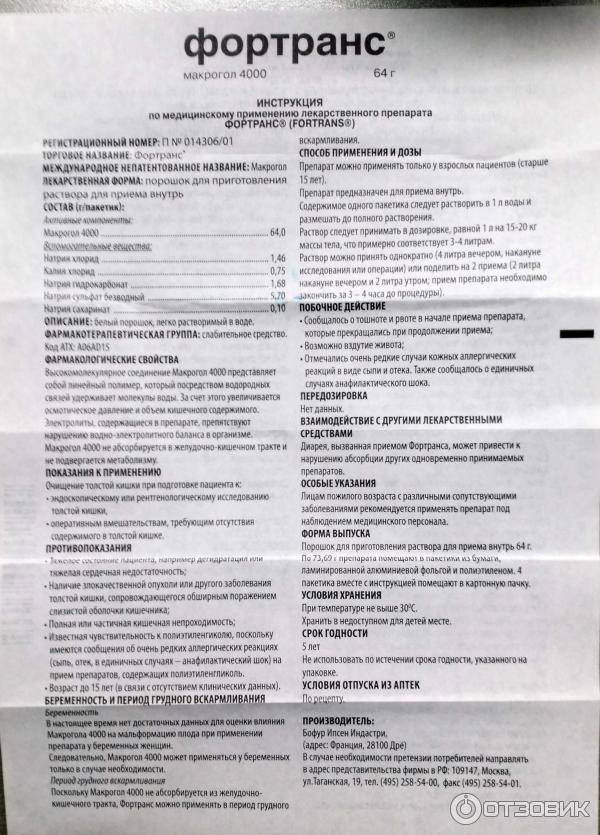

Подготовка к ирригоскопии: необходимые препараты